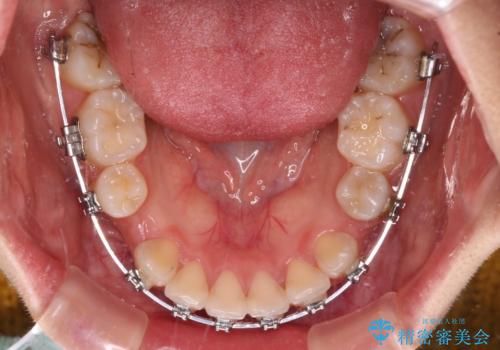

- メタルブラケット

地元で矯正治療を始める予定で上顎左右第1小臼歯2本を抜歯したものの、その後転居したため治療が滞っているとのことでした。

上下ともに歯列が前方に突出していたため、上下左右の第一小臼歯4本を抜去する方針(既に上顎は抜歯されています)で、ワイヤー装置による矯正治療を行うこととしました。